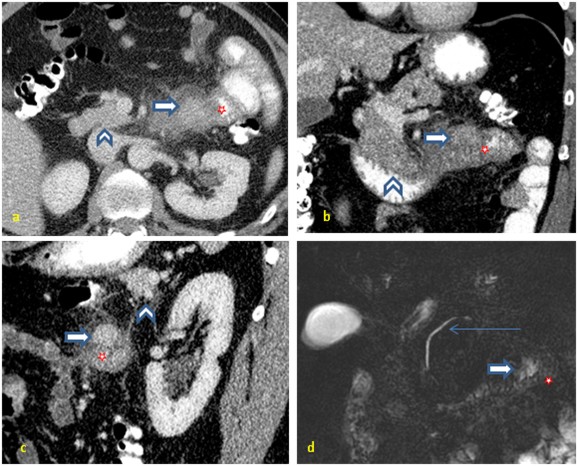

In the ER, CT examination was performed on a 256-slice dual source scanner (SOMATOM Definition Flash, Siemens Medical Solution). Contrast-enhanced CT in venous phase (80 sec delay) was done after intravenous administration of 80 cc of Omnipaque 300 (iohexol with iodine content of 300 mg/mL). The datasets were reconstructed with slice-thickness of 5mm in axial, coronal and sagittal planes. The images demonstrated a focal mass measuring 2.5 x 2.8 cm, located at the duodenojejunal flexure and separate from normal appearing pancreatic body (Figure 1a-c). Additionally, there was focal, moderate jejunal wall thickening and adjacent mesenteric fat stranding. The constellation of these findings suggested a submucosal tumor or jejunal diverticulitis.

Figure 1. Contrast-enhanced CT in portal venous phase (a-c) shows a jejunal mass (block arrow) with density similar to the normal native pancreatic density (arrowhead). Note the adjacent edematous thick wall duodenum and proximal jejunum. (d) MRCP demonstrates the relation between native pancreas (thin long arrow-main pancreatic duct) and ectopic pancreas near the duodenojejunal flexure. No accessory duct was demonstrated in this case. Jejunum is marked as¶. |